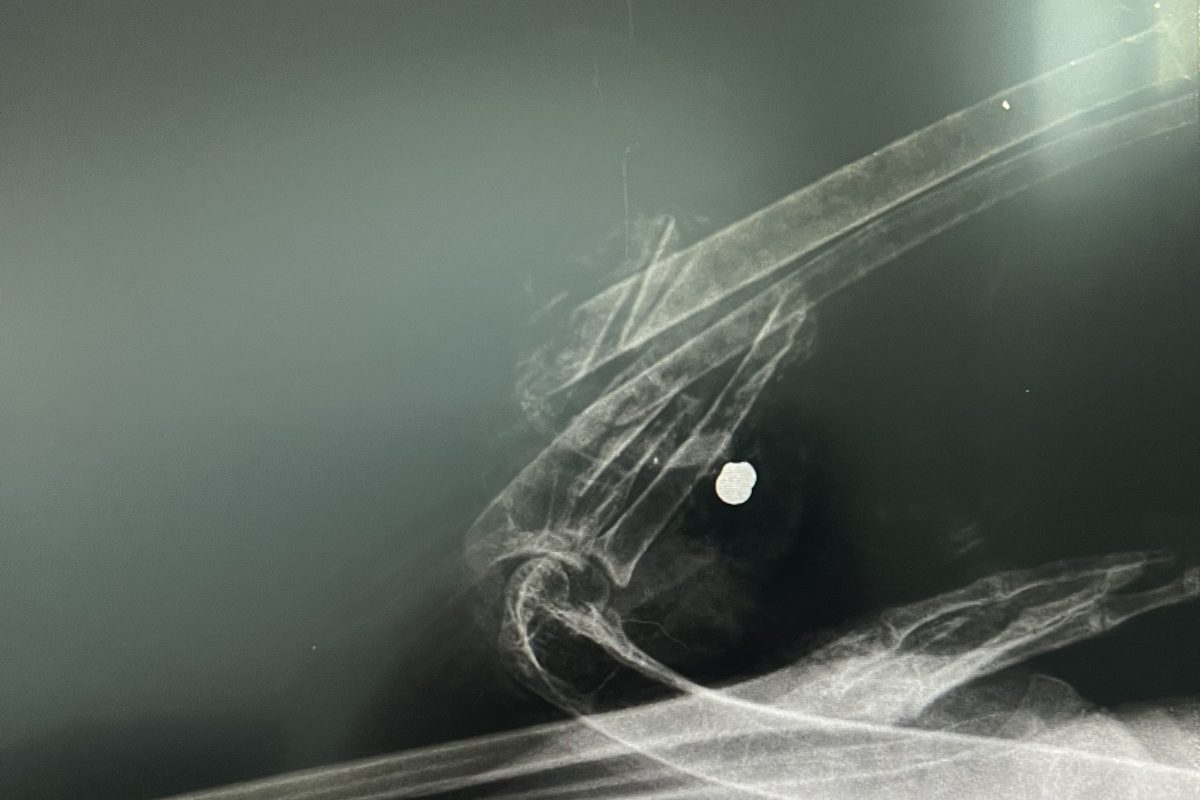

| Primer ustreljene bele štorklje (Ciconia ciconia) v Slovenski Bistrici Dne 14. 8. 2025 je bila v ambulanto nacionalnega zatočišča za prostoživeče živali Golob d.o.o. na Muti sprejeta odrasla bela štorklja, najdena na območju Slovenske Bistrice. Klinične ugotovitve ob sprejemu: • odrasel osebek v dobri telesni kondiciji (telesna masa 3.400 g, dobro razvite prsne mišice, normalna operjenost letalnih in repnih peres, ter nepoškodovana obrisna krovna peresa telesa, zdravi medenični končini), • odprti zlom komolčnice in koželjnice leve peruti, • obsežna raztrganina letalnih mišic z izgubo tkiva, • sekundarna bakterijska infekcija poškodovanega tkiva, razvoj miaze in vlažne gangrene (Gangrena humida), • RTG-diagnostika je potrdila prisotnost svinčene krogle v proksimalnem segmentu podlakti, ki je povzročila strelno lezijo z obsežnim poškodovanjem kostnih in mišičnih struktur. Sekundarno je zaradi padca z obcestne svetilke nastopila dodatna travmatska poškodba peruti. Poškodbe so povzročile obsežno nekrozo, izgubo krvi, septično in hipovolemično stanje s šokom, kar je bil neposredni vzrok pogina. Oskrba ob sprejemu: Izvedena je bila stabilizacija s tekočinsko terapijo, protibolečinska in protivnetna terapija, antibiotično zdravljenje, toaleta rane ter hranjenje po sondi. Kljub intenzivni oskrbi je žival zaradi obsežnih poškodb poginila. Primer je bil skladno s protokolom predan v nadaljnjo obravnavo na Veterinarsko fakulteto (raztelezba). Opomba: Do tega trenutka primera nismo javno komentirali, saj smo želeli dosledno spoštovati strokovne in pravne protokole. Prvotne informacije so bile nemudoma posredovane pristojnim organom. Naše stališče: Strel v belo štorkljo, ki je v Sloveniji in Evropi strogo zavarovana vrsta, razumemo kot nesprejemljivo dejanje, ki nima nikakršnega opravičila. Takšna ravnanja pomenijo neposredno ogrožanje prostoživečih živali ter hkrati kršitev nacionalne in evropske zakonodaje. Kot strokovna institucija menimo, da morajo biti takšna dejanja dosledno preiskana, odgovorne osebe pa ustrezno sankcionirane. Naš namen ni le obravnava posameznih primerov, ampak tudi opozarjanje družbe, da ima zaščita prostoživečih živali širši pomen za ohranitev biotske raznovrstnosti in naravne dediščine Slovenije. |